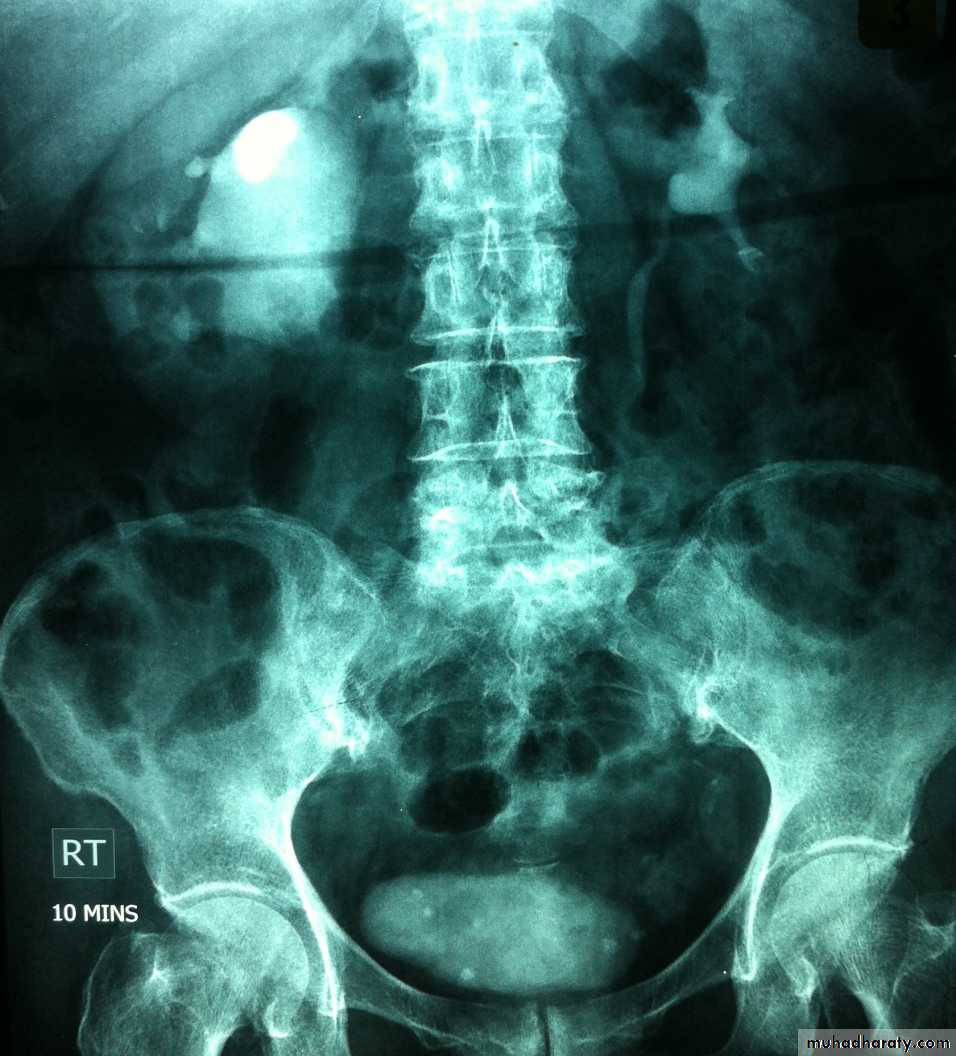

IVU :

- There is rounded or elliptical dilatation of lower end of ureter with thin lineal filling defect around it , resembling (cobra head appearance),

- Proximal dilatation of rest of ureter .

- In advanced cases hydronephrosis .

- In obstructed ureterocele , filling defect in the bladder